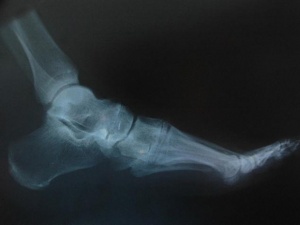

Kırıkların tedavisinde ipek vidalar kullanıldı

Bilim adamları, kırılan kemiklerin tedavisinde yüzde 100 ipekten yapılmış vidaları kullandı.

Sonuçları Nature Communications dergisinde yayımlanan araştırmada, yüzde 100 ipekten yapılmış vidaların, fareler üzerinde kırıkların tedavisi için kullanıldığı belirtildi.

ABD'deki Tufts Üniversitesi'nde görevli bilim adamları, özel kalıplar yardımıyla tıbbı kullanıma uygun ipekten vidalar yaptı ve bu vidalar, farelerin bacaklarının arkasında kırılan noktalara yerleştirildi. İpekten vidalar, kemikleri başarılı bir şekilde bir arada tuttu ve araştırmanın sonunda da çözünmeye başladı.

İpek, sertliğinin kemiğe benzemesi ve vücutta eriyerek yok olması özelliği dolayısıyla geleneksel metal plakalar ve vidalarla karşılaştırıldığında ümit verici bir biyomühendislik malzemesi olarak kabul ediliyor.